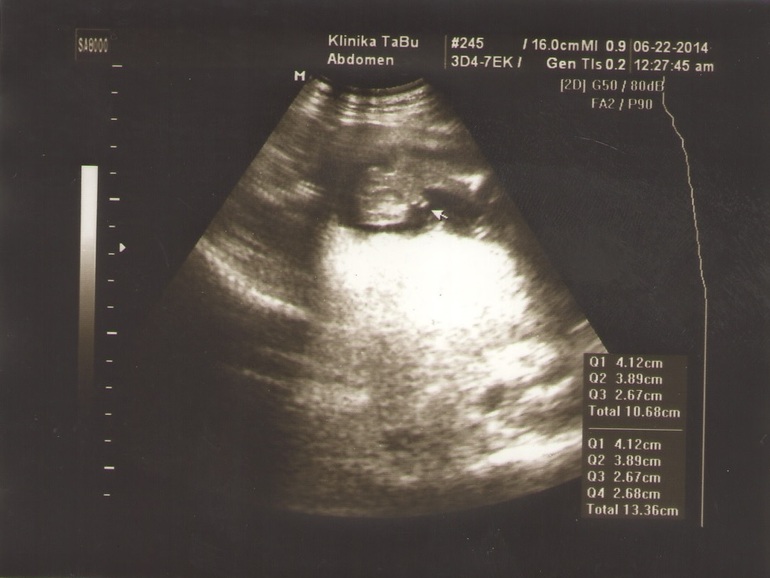

Другие вот:

Тут писюн на одном а на другом голова вид сверху и ручки. Врач наверное вообще не знает как надо фотографировать!)))